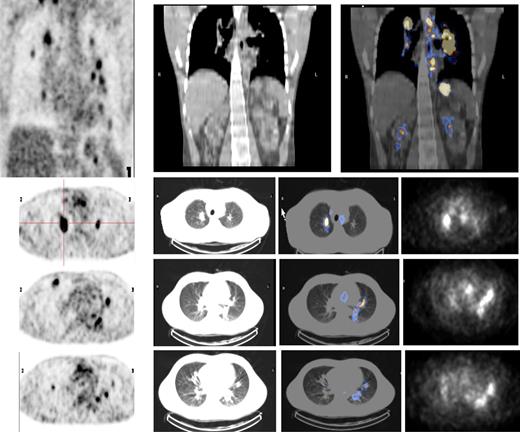

Both HL patients also showed favorable lesion/bone marrow dosimetry estimates after receiving diagnostic 131I-L19SIP, with an absorbed dose of radioactivity to the target lesions—a pulmonary lymphoma lesion (patient HL1) and a left basal pulmonary lesion and a right axillar lymphoma conglomerate (patient HL2)—estimated to be approximately 14 and 22.7 Gy, respectively. The absorbed dose to the red bone marrow was calculated to be 1.3 and 0.85 Gy for HL patients HL1 and HL2, respectively. In HL patient HL1, the SPECT-CT images acquired 12 days after a dose of 5.55 GBq 131I-L19SIP demonstrated selective ED-B FN targeting in multiple parenchymal lung lesions and in enlarged supraclavicular and lumboaortic lymph nodes with all such sites corresponding to high 18F-FDG uptake on baseline PET-CT scans (Figure 6). In the second HL patient (HL2), the SPECT-CT images acquired 12 days after a dose of 3.7 GBq 131I-L19SIP demonstrated selective ED-B FN targeting in multiple enlarged axillar and supraclavicular (both sides), paratracheal, subcarinal, pleural, as well as peritoneal and iliacal (both sides) lymph nodes. ED-B FN–expressing lymphoma lesions were also found in the right and left basal lobes of the lung. All ED-B FN–expressing lymphoma lesions corresponded to high 18F-FDG uptake on baseline PET-CT scans (Figure 7). Both HL patients experienced a partial clinical response according to RESCIST criteria at 1 month after therapy with shrinkage of the sum of diameters of the measurable lymphoma lesions of 44% (134 to 75 mm; baseline to 1 month after treatment) and 39% (417 to 256 mm) for patients HL1 and HL2, respectively. This partial response was confirmed at 2 and 3 months after 131I-L19SIP therapy for both HL patients. The 3 lymphoma patients did not experience any acute toxicity during or after 131I-L19SIP therapy. Mild and transient thrombocytopenia was observed in both HL patients, but not in the SLL NHL patient, with a nadir of 22 and 52 × 109 platelets/L for patients HL1 and HL2, respectively, at 6 weeks after 131I-L19SIP injection.

Objective partial remission in another advanced Hodgkin lymphoma patient (HL2) induced by 131I-L19SIP radioimmunotherapy. (A) 18F-FDG PET scans show intense glucose metabolism in multiple enlarged lymph nodes, particularly in right and left axillary and supraclavicular nodes, in paratracheal, subcarinal, peritoneal, and iliacal nodes as well as in lymphoma lesions located in the basal lobes of both lungs (leftmost image). One (center) and 2 (rightmost image) months after application of therapeutic 131I-L19SIP (3.7 GBq), the number and size of active lymphoma lesions decreased substantially. (B) 18F-FDG PET scans and 131I-L19SIP SPECT-CT images from the same patient. Transaxial SPECT-CT images (top row) show selective 131I-L19SIP uptake to a pulmonary lymphoma lesion still detectable 12 days after injecting a therapeutic dose (3.7 GBq). Transaxial 18F-FDG PET scans captured prior to (second row), 1 month after (third row) and 2 months after (bottommost row) application of therapeutic 131I-L19SIP show a significant shrinkage in size and a complete disappearance of metabolic activity in the initially large pulmonary lymphoma lesion, indicative of lymphoma response to 131I-L19SIP radioimmunotherapy.